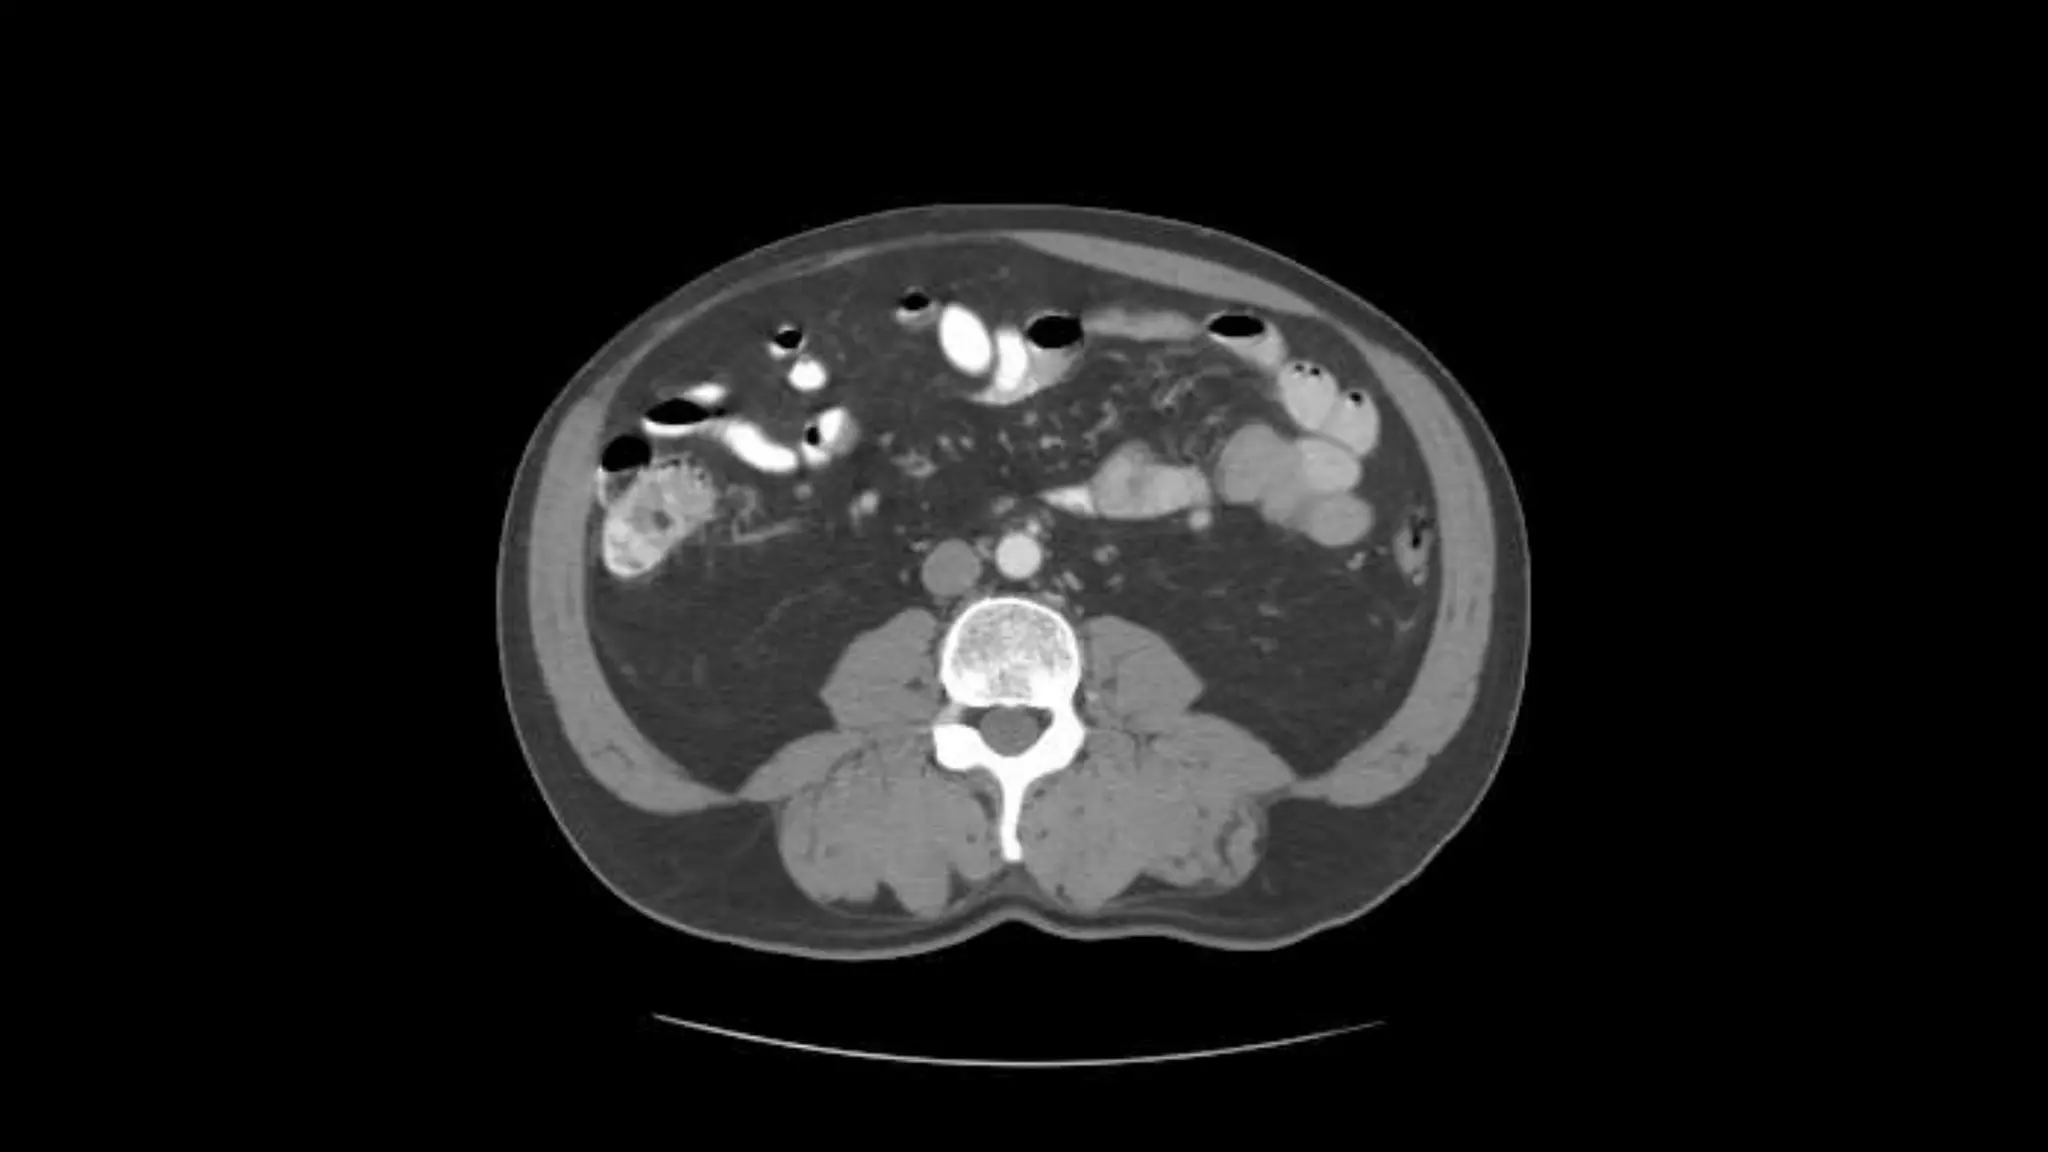

Superior Mesenteric Vein – follow it up as it joins the Splenic

Vein to form the Portal Vein

Superior Mesenteric Vein– follow it up as it joins the Splenic Vein to form the Portal Vein